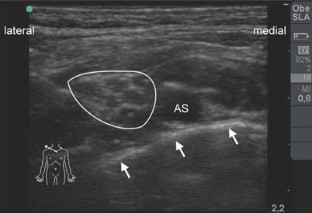

Abb. 1